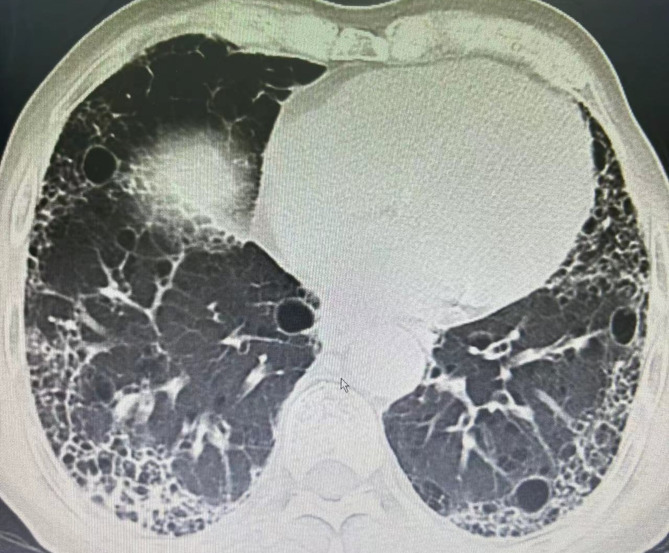

Sjögren's syndrome (SS) is a chronic systemic autoimmune disease mainly involving exocrine glands and particularly affecting the salivary glands and lacrimal glands, thus inducing a dry mouth and dry eyes. Extraglandular organs are also involved in SS, and this results in damage to multiple systems. Among these, lung damage is more common, with high morbidity and mortality rates, and the lack of typical symptoms in the early stages makes it challenging to identify it. The main pulmonary manifestations of SS are bronchitis, pulmonary hypertension, pulmonary cysts, pulmonary amyloidosis, interstitial pneumonia, and pulmonary fibrosis. Cystic lung disease affects about 4-46.2% of patients with SS. The imaging characteristics of pulmonary cysts in SS, including the size, number, morphology, and distribution, as well as differential diagnosis, mechanisms underlying the formation of pulmonary cysts, and current treatment strategies, are presented in this review.